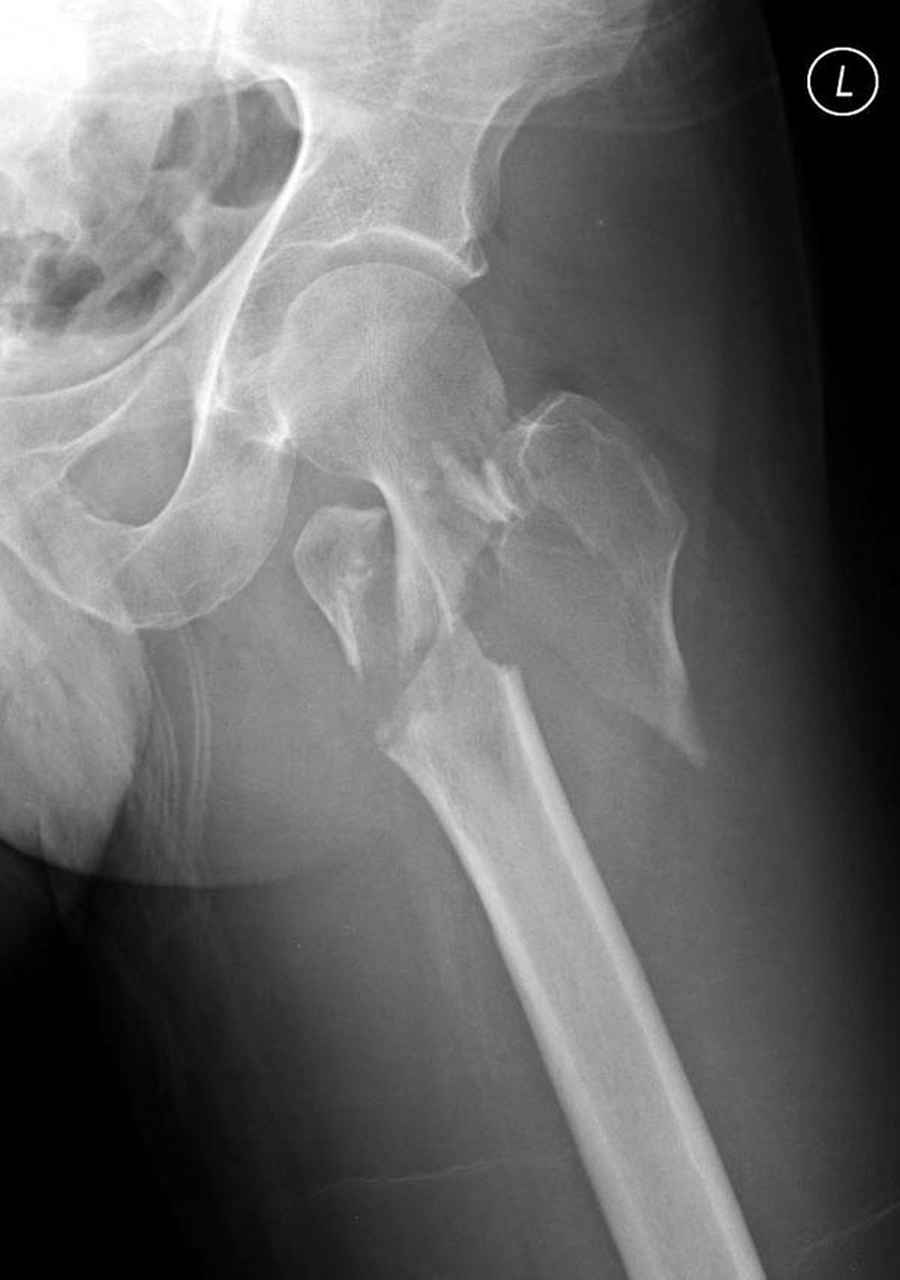

Думаю что перелом всетаки оскольчатый межвертельный, скорее всего использовали бы реконструктивный штифт, но возможно и DHS.

По нашему мнению линия перелома проходит вверху через латеральный отдел шейки бедра, вертельная область состоит из нескольких фрагментов. В таких условиях применить DHS или дистальную бедренную пластину LCP представляется нам сомнительным. Закрытый остеосинтез проксимальным гамма-гвоздем или PFNa невозможен т.к. нет ЭОПа.

Прилагаю Р-ы на вытяжении.